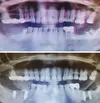

أكياس الفك

علاج الزرع السني

التهاب ما حول الزرعة السنية (Periimplantitis)

التهاب مخاطية ما حول الزرعة (Peri-Implant Mukozitis)